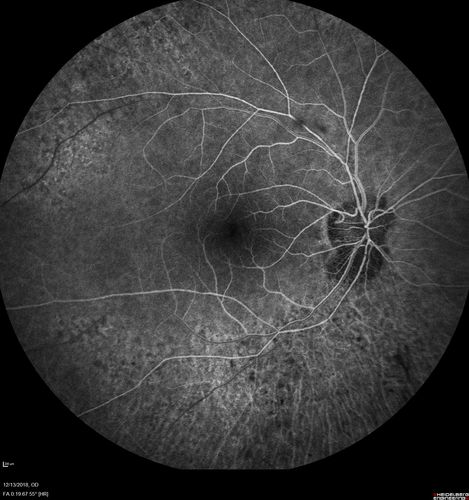

Retinitis Pigmentosa with Cystoid Macular Edema responsive to topical carbonic anhydrase inhibitors

67 year old female  She thought it was time to have her glasses changed.She has no family history of reitnal disease and has never been diagnosed with a problem.   She started having night vision trouble the last year.  Two sisters and a brother with normal vision.